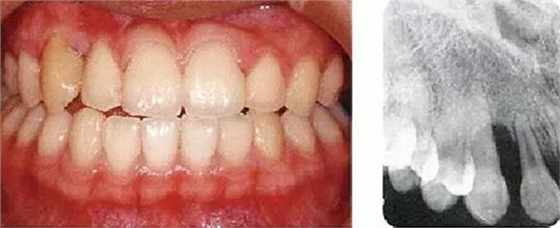

●參考病例① 35歲女性

35歲女性。妊娠4個(gè)月。過(guò)去雖然接受過(guò)刷牙指導(dǎo),但菌斑控制狀態(tài)依然不理想?;颊哂邪l(fā)現(xiàn)自己刷牙時(shí)牙齦出血。

●參考病例② 25歲女性

25歲女性。菌斑控制狀態(tài)不好。齦溝除磨牙處外全在3mm以下,X光照片上左上、右下、左下的第一磨牙上有垂直性骨吸收。這個(gè)病例是參考病例①10年前的狀態(tài),是典型的侵襲性牙周炎局部型。